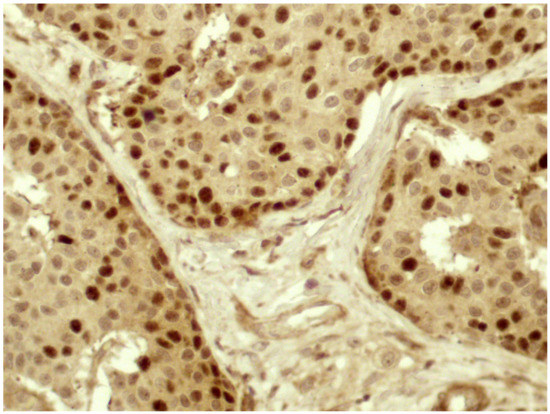

Slug protein was expressed only in pancreatic neoplasms and was found to be homogeneously negative in all other locations. It showed cytoplasmic signal in 9 cases and the score was 1 in 2 cases, 2 in 3 cases, and 3 in 4 cases. Immunoreactivity was also observed in perilesional pancreatic tissue, but only in endocrine cells (Figure 5a–c). No association was detected between the immunoscore and the clinico-pathological parameters such as age, sex, site (head vs. corpus/tail), and stage. The most evident finding was a direct association between Slug lost/reduced expression and a higher grading (p value = 0.0033) (Figure 6), as well as an inverse correlation between Slug immunoscore and Ki67 L.I. (p value= 0.0058, r= −0.6073) and Twist (p value = 0.0030, r = −0.6428), using a Spearman’s exact test (Figure 4).

Figure 5.

Slug immunoscore—(a) an intense cytoplasmic immunoreaction was evident in the normal pancreatic tissue that was located exclusively in the neuroendocrine compartment. Negative scores were exocrine pancreas (20× magnification); (b) cytoplasmic signal was observed in 15–50% of neoplastic cells (20× magnification); (c) in this field, strong and diffuse (>50%) immunoreaction was detected in neoplastic cells (40× magnification); (d) 20× magnification, and (e) 40× magnification. E-cadherin expression was reduced compared to cases where the expression was preserved (f) 40× magnification.